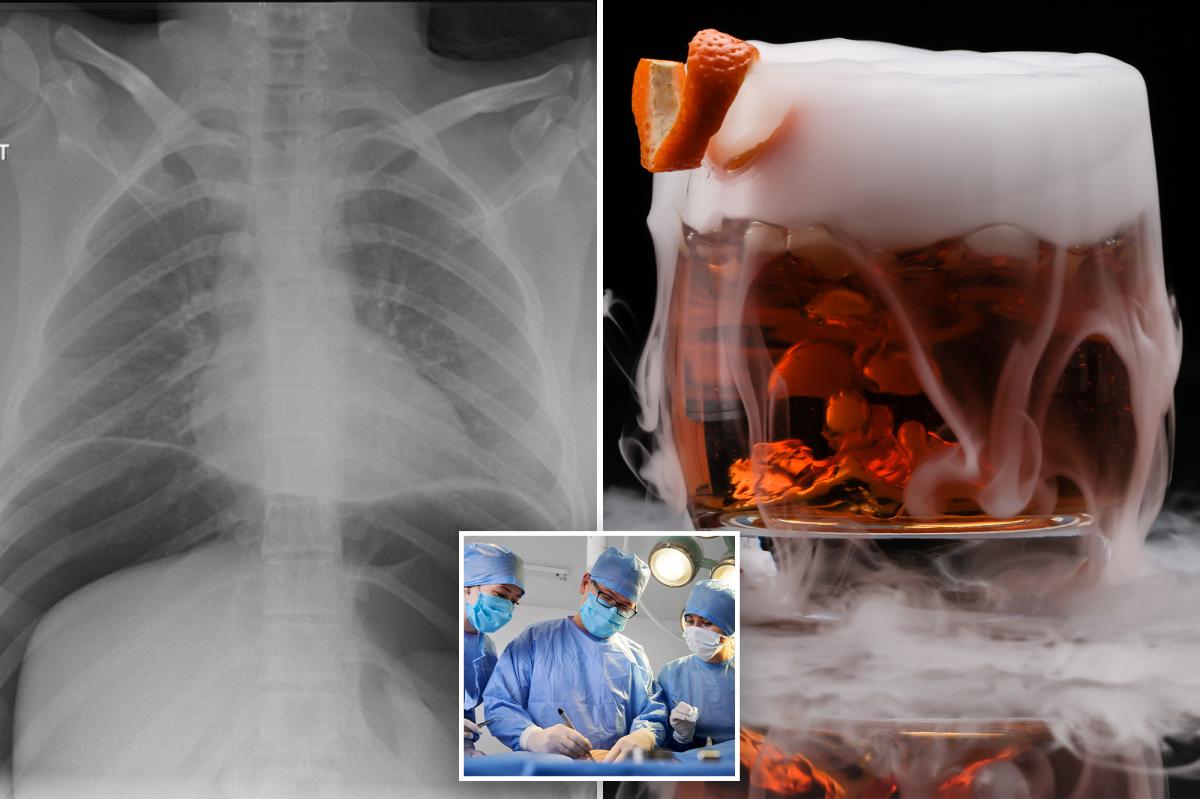

يتضمن منشور Trebach صورة بالأشعة السينية تم التقاطها لمريض يبلغ من العمر 18 عامًا تم إدخاله إلى غرفة الطوارئ بعد شرب مشروب كحولي يحتوي على نيتروجين سائل.

وقد نُشرت تفاصيل إصابتها سابقًا في تقرير حالة من مستشفى لانكستر الملكي في لانكستر بالمملكة المتحدة.

مباشرة بعد تناول مشروبها، أبلغت المريضة عن آلام شديدة في البطن وضيق في التنفس.

وكشف المزيد من الفحص، بما في ذلك الأشعة المقطعية، عن إصابتها بثقب في المعدة. أجرى الأطباء عملية جراحية طارئة لمعالجة خرق البطن.